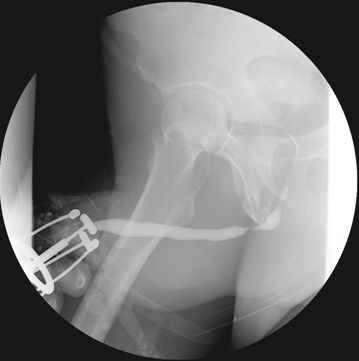

병력 청취가 중요하다. 과거 요도가 손상된 이력이 있는지, 도뇨관을 꽂았던 과거력이 있는지, 또한 임균성 요도염으로 치료받은 과거력, 전립선 비대증 등으로 레이저를 포함한 내시경적 수술을 한 수술력 등이 있는지 확인하고, 현재 배뇨양상을 문진한다. 요류검사를 통해 소변이 배출되는 속도를 측정한다. 역행성요도조영술과 배뇨 중 방광요도조영술을 통해 좁아진 부위와 길이를 측정한다. 방광요도내시경은 좁아진 부위를 통과하기 힘들기 때문에 진단적 검사에 잘 이용되지 않는다.

역행성 요도조영술상 좁아진 요도